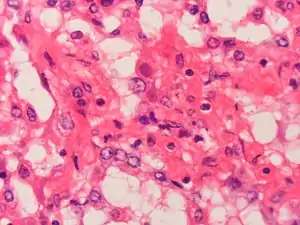

Adenovirus can cause severe necrotizing pneumonia in which all or part of a lung has increased translucency radiographically, which is called Swyer-James Syndrome.[21] Severe adenovirus pneumonia also may result in bronchiolitis obliterans, a subacute inflammatory process in which the small airways are replaced by scar tissue, resulting in a reduction in lung volume and lung compliance.[21]